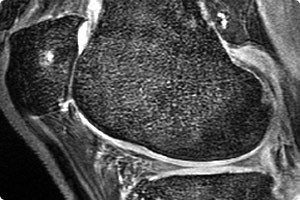

bedeutendsten Volkskrankheiten unserer Zeit. Sie geht mit einer Zerstörung des Gelenkknorpels einher und kann prinzipiell jedes Gelenk betreffen, jedoch sind das Knie und Hüftgelenk am häufigsten betroffen, gefolgt vom oberen Sprunggelenk, Schulter, Ellenbogen und Hand. Es ist eine Erkrankung, die mit schmerzhaften Einschränkungen der Gelenkbeweglichkeit einhergeht und letztlich zu einem Verlust der Selbstständigkeit führt.